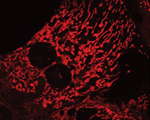

Estudis previs realitzats a l’IRB Barcelona van demostrar que persones obeses i diabètiques de tipus 2 tenien nivells molt baixos de Mitofusina 2 en múscul. Aquesta proteïna controla la via de senyalització de la insulina al fetge i els músculs. Els científics han observat que la seva carència provoca alteracions a les mitocòndries i el reticle endoplasmàtic, dos orgànuls fonamentals per al bon funcionament cel·lular. “Hem demostrat que l’acumulació de disfuncions en aquestes dues peces altera el comportament de les cèl·lules i afavoreix l’aparició de condicions de pre-diabetis”, diuen els principals autors de l’article, David Sebastián i María Isabel Hernández-Álvarez, científics postdoctorals de l’equip de Zorzano.